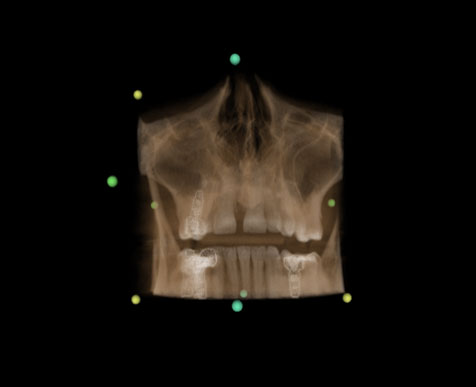

Automatic AI panoramic curve